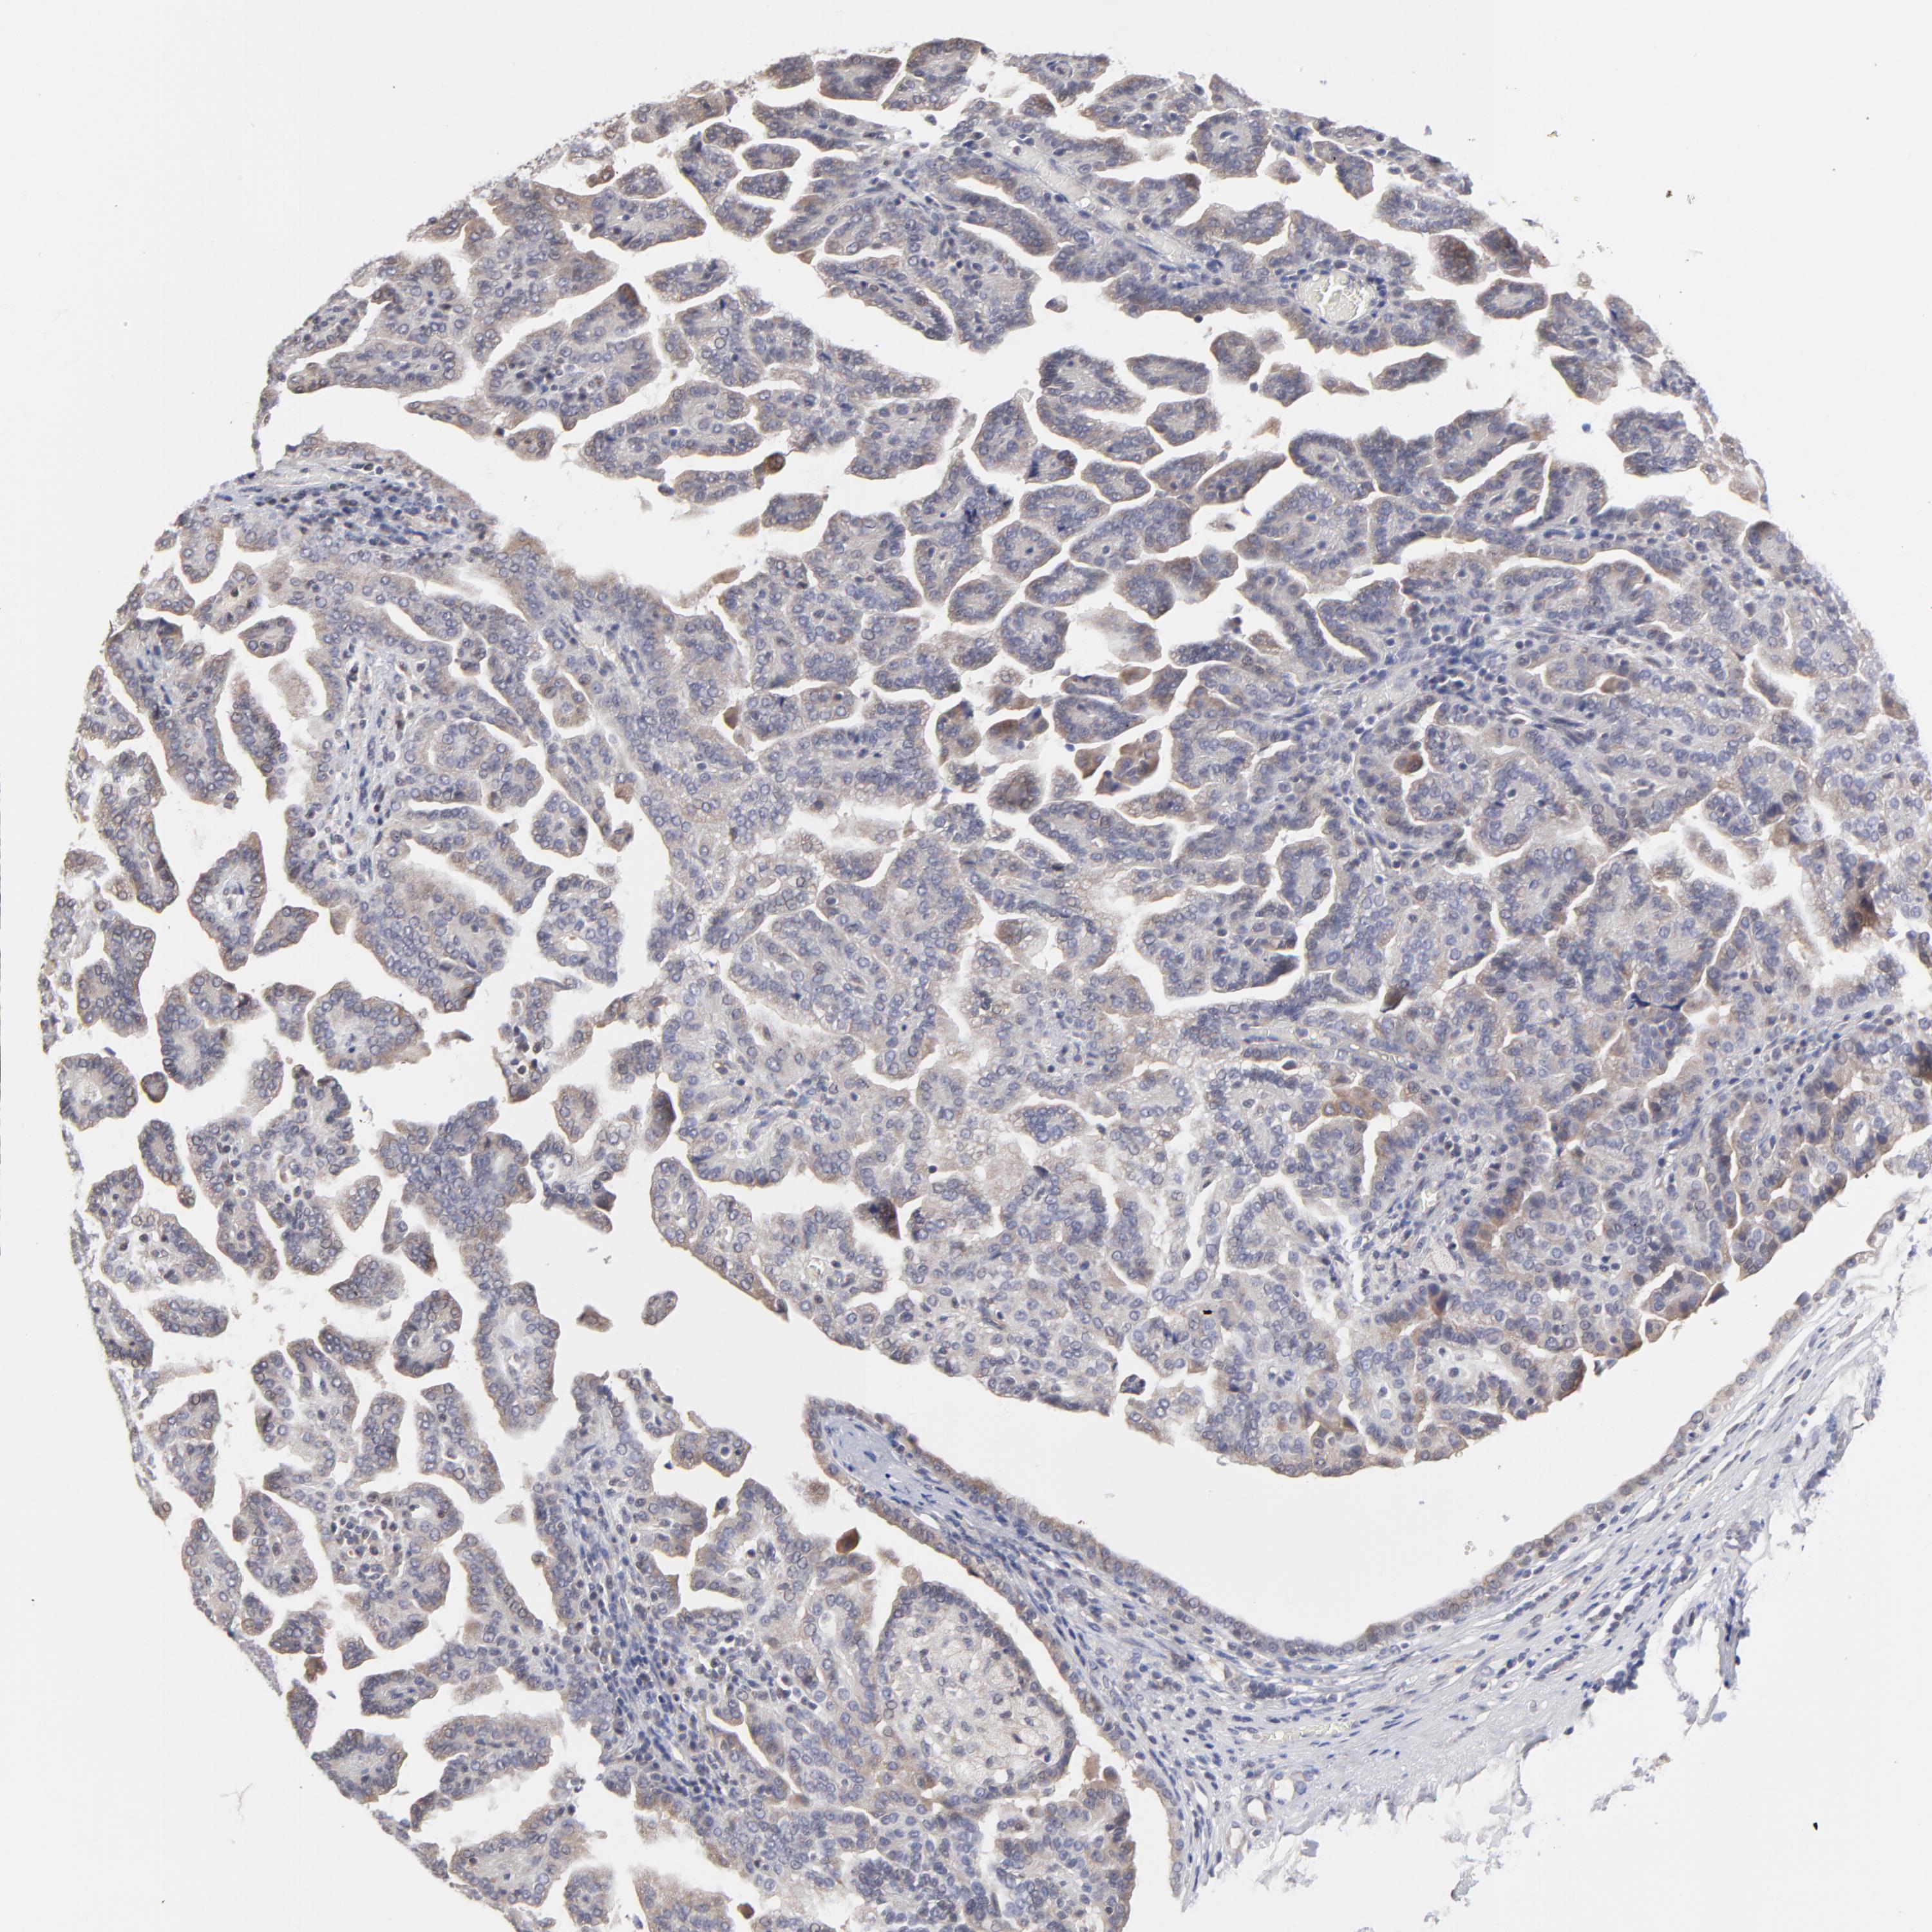

ZNF157

CANCER RENAL CANCER Show tissue menu

Renal cancer

Kidney chromophobe